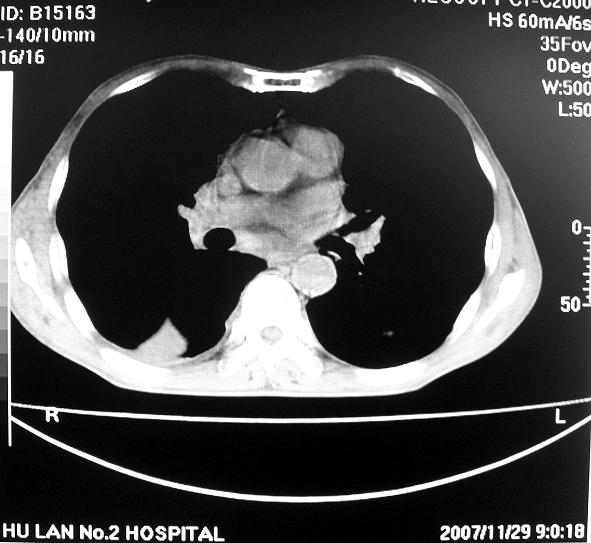

男63岁胸痛来诊

右下肺周围性肺ca并双肺及右侧胸膜转移。[emb6]

右肺病灶前缘不平整,略呈分叶状,其后方胸膜下脂线消失且似有向胸壁浸犯,左下肺球形灶内可见不规则空洞影,余双肺内可见多枚结节影,结合病史支持考虑肺癌肺内转移胸膜转移,便双肺后部病灶倒也是结核好发区域,建议穿刺活检

右下肺周围性肺ca并双肺及右侧胸膜转移。支持

右下肺周围性肺ca并双肺及右侧胸膜转移。

右下肺周围性肺ca并双肺及右侧胸膜转移。单看病变像炎性假瘤。

右下肺癌,双肺及胸膜转移

右下肺癌伴双肺及胸膜转移。

[quote]以下是引用余辉在2007-12-2 20:29:00的发言:[br]右肺病灶前缘不平整,略呈分叶状,其后方胸膜下脂线消失且似有向胸壁浸犯,左下肺球形灶内可见不规则空洞影,余双肺内可见多枚结节影,结合病史支持考虑肺癌肺内转移胸膜转移。

左肺病灶内可见空泡征及典型的胸膜牵拉征,不排除原发周围型肺癌的可能.